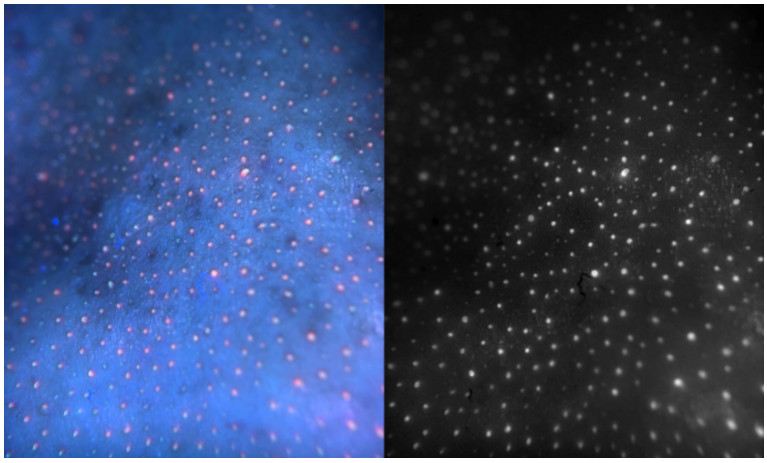

عکس هایی از گوشی هوشمند اصلاح شده که محققان برای گرفتن تصاویر RGB با نور LED از پوست و حفره های دهان استفاده کردند

در سمت چپ یک تصویر رنگی باکتری ها را به عنوان نقاط قرمز در یک فضای آبی نشان می دهد. در سمت راست همان تصویر به صورت سیاه و سفید نشان داده می شود.

محققان گفتند که چراغ های LED گروهی از مولکول های مشتق شده از باکتری به نام پورفیرین را تحریک می کند و باعث می شود که آنها سیگنال فلورسنت قرمز رنگی را منتشر کنند. سایر اجزای موجود در تصویر مانند پروتئین ها یا مولکول های روغنی که بدن ما تولید می کند، همچنین پوست، دندان ها و لثه ها تحت LED قرمز نمی درخشند.